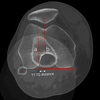

An 18-year-old man sustains a twisting injury to the left knee while playing football. An MRI scan is shown in Figure 48. What is the most likely diagnosis?

MRI scan shows a displaced, bucket-handle lateral meniscus tear. The sagittal view shows the typical “large anterior horn” sign, or “double meniscus” sign in which the displaced bucket-handle fragment appears just anterior to the native anterior horn of the lateral meniscus. The presence of the fibula on the sagittal view confirms this as the lateral compartment. The image is lateral and the cruciate ligaments are not visualized. The articular cartilage shown does not demonstrate an osteochondral lesion.